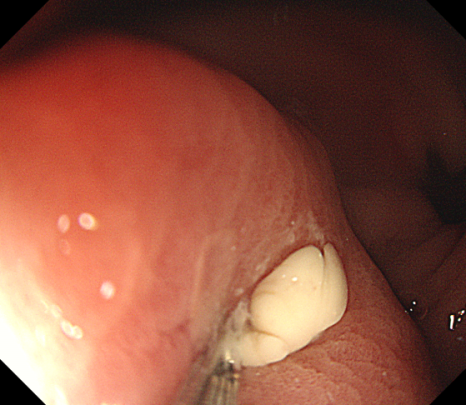

一周后复查胃镜:恢复正常

于主任带领团队在超声内镜的定位下,穿刺针避开大血管,精准刺入胃脓肿腔内,抽出脓液约0.5ml;并留置引流管持续引流。术后王女士腹痛等症状马上缓解。回家口服消炎药一周后来院复查,胃镜显示手术部位恢复正常。